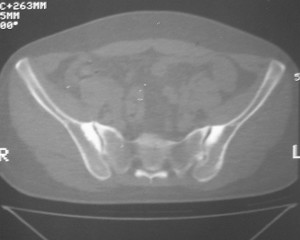

标题: CT7246: F,30岁,下腰痛,同事的片子,请老师们看看,初 [打印本页]

标题: CT7246: F,30岁,下腰痛,同事的片子,请老师们看看,初

典型的致密性髂骨炎

典型的双侧骶髂关节致密性骨炎.

何谓髂骨致密性骨炎?髂骨致密性骨炎是发生于髂骨耳状关节部分的骨质密度增高性疾病。病因迄今不明,可能与妊娠、机械性劳损、病灶性炎症有关。本病好发于20~35岁的育龄妇女,偶见男性。

髂骨致密性骨炎的临床表现与体征:腰骶部疼痛,多呈慢性、间歇性酸痛、隐痛,可向一侧或双侧臀部及大腿后侧扩散,但不沿坐骨神经方向放射,步行、站立、负重及劳累后加重,咳嗽、打喷嚏不能使疼痛明显加重,休息后症状减轻。患者腰骶角加大,局部有压痛和肌紧张,骨盆分离和挤压试验阳性,“4”字试验阳性,化验检查多在正常范围内。x线检查,骶髂关节间隙整齐清晰,靠近骶髂关节面中的髂骨耳状关节部分骨质密度增高,呈均匀浓白边缘清晰的骨质致密带,骨小梁消失,无骨质破坏。本病应注意与早期强直性脊柱炎、骶髂关节结核相鉴别。